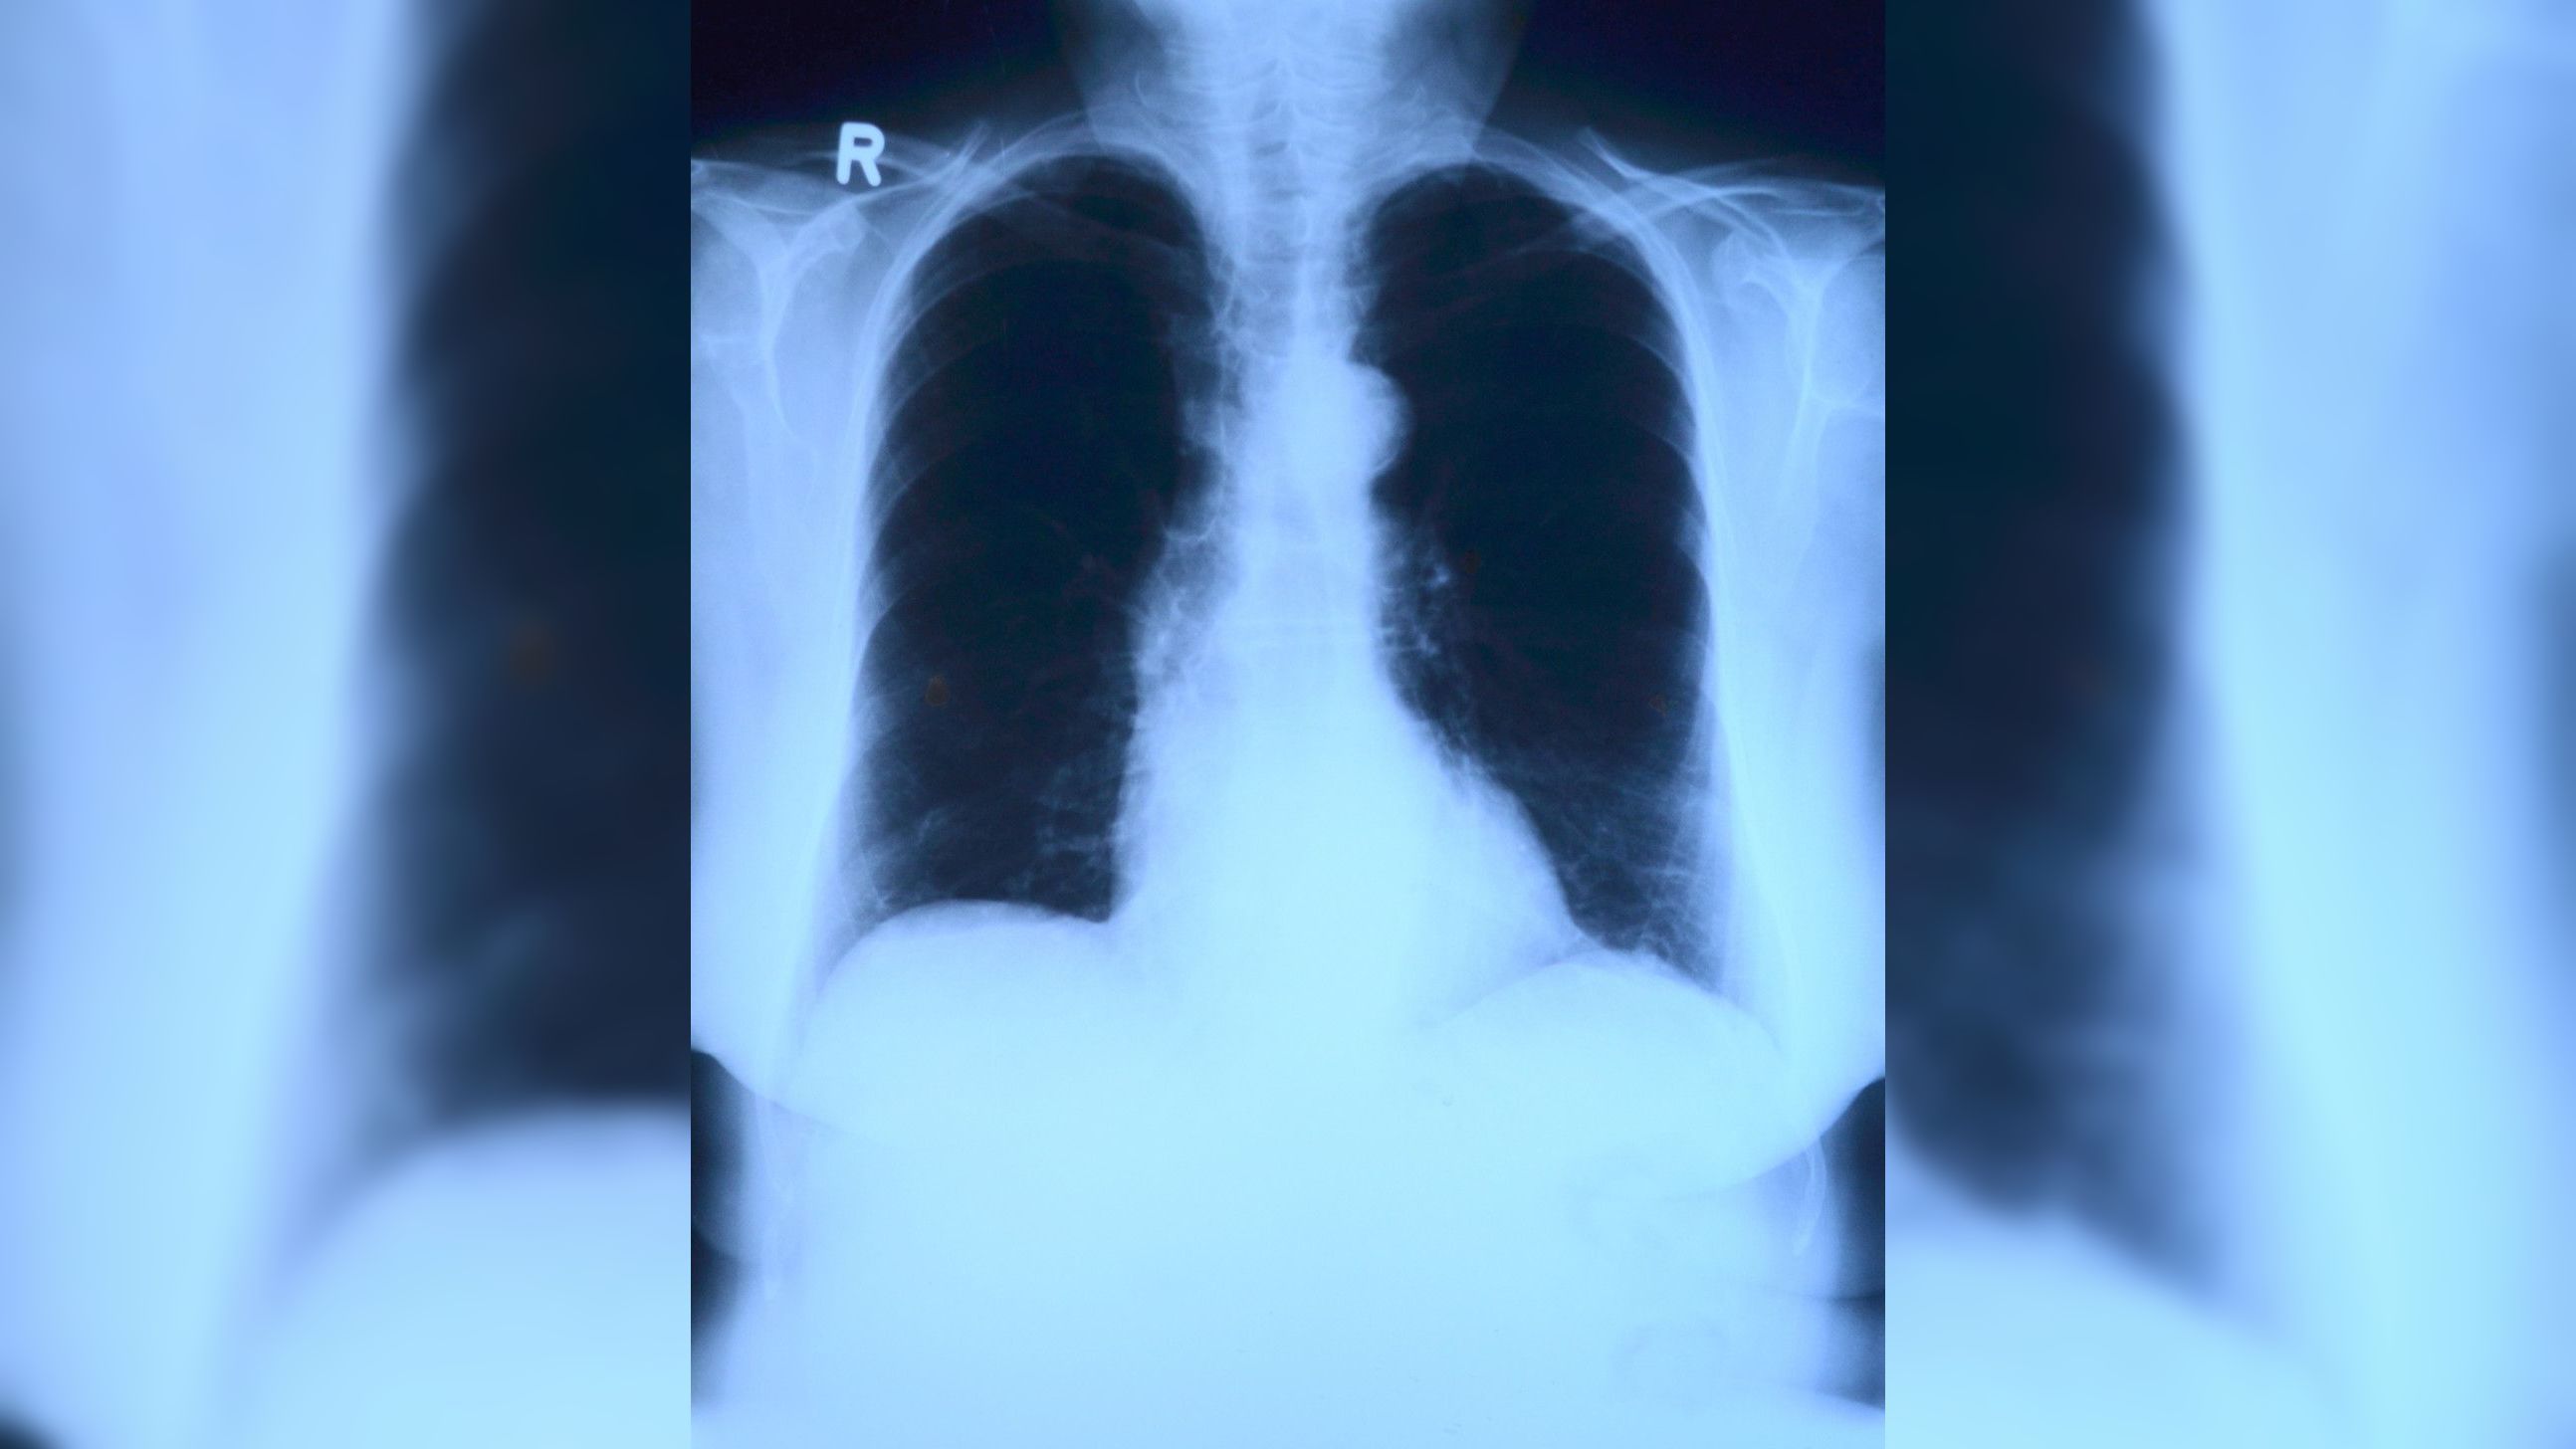

Что такое двусторонняя лимфоаденопатия? Диагностика и лечение